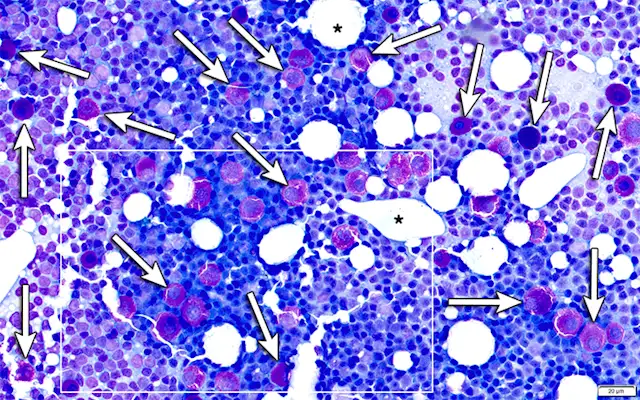

There were no significant abnormalities on CBC and serum chemistry profile. Premedication with diphenhydramine (2 mg/kg IM) was administered prior to fine-needle aspiration of the mass and mandibular lymph node. Cytology of the mass was highly cellular and composed predominantly of variably granulated mast cells (Figure 2). There was mild to moderate anisocytosis and mild anisokaryosis. Binucleated cells were frequent.

FIGURE 2

Fine-needle aspirate of the subcutaneous, periorbital mass showing a sample composed predominantly of variably granulated mast cells. Well-granulated (solid arrows) and poorly granulated (circles) mast cells can be seen. Eosinophils (arrowheads), macrophages (asterisk), and occasional lymphocytes (curved arrow) and spindle cells (dashed arrow) consistent with reactive fibroblasts are also present. No mitotic figures were identified. Modified Wright’s stain, 1,000× magnification